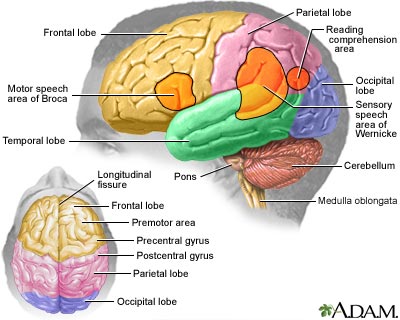

An area of your body, usually the groin or wrist, is cleaned and numbed with a numbing medicine (local anesthetic). A thin, hollow tube called a catheter is placed through an artery. The catheter is carefully moved up through the main blood vessels into an artery in the neck. X-rays help your health care provider (usually a specially trained radiologist) guide the catheter to the correct position.

Once the catheter is in place, dye is sent through the catheter. X-ray images are taken to see how the dye moves through the artery and blood vessels of the brain. The dye helps highlight any blockages in blood flow.

Cerebral angiography is most often used to identify or confirm problems with the blood vessels in or around the brain.

Your provider may order this test if you have symptoms or signs of:

- Abnormal blood vessels in the brain (vascular malformation)

- Bulging blood vessel in the brain (aneurysm)

- Narrowing of the arteries in the brain

- Inflammation of the blood vessels in the brain (vasculitis)